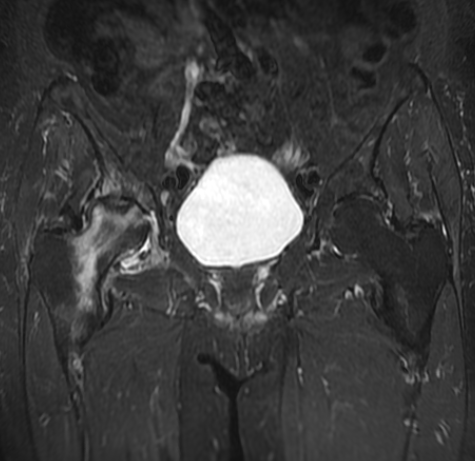

1 Essential Osteonecrosis Hip MRI Diagnosis London Guide

Osteonecrosis hip mri diagnosis london requires expert diagnosis and management. If you have had hip pain for three months or...